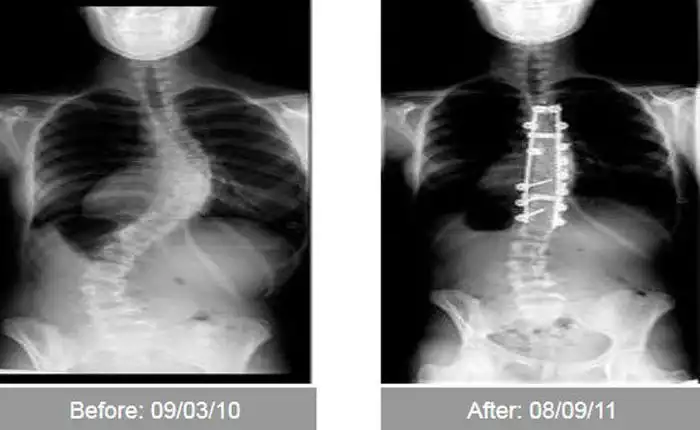

Эти сравнительные снимки в очередной раз доказывают,

что при желании можно серьезно изменить свой внешний вид,

причем, как в лучшую сторону, так и в худшую ;)